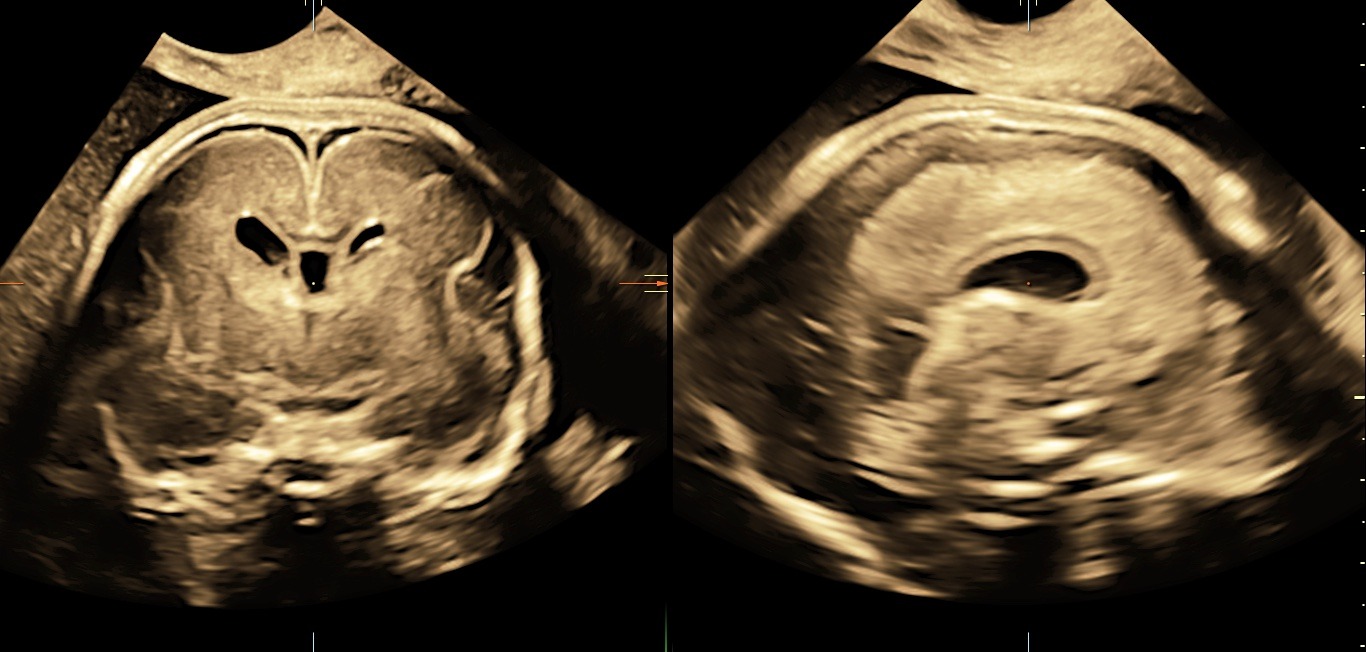

„VolusonTM Expert 22 je přístrojem, který disponuje nejmodernějšími technologiemi pro zobrazování plodu ultrazvukem. Vysoká kvalita obrazu zaručuje mimořádně detailní a přesné zobrazení jednotlivých struktur plodu včetně jeho cévního zásobení. Tyto parametry nejen že zvyšují přesnost naší diagnostiky, ale hlavně posouvají naše možnosti záchytu vrozených vad do časnějších fází těhotenství. Kvalitní 3D/4D technologie zaručuje precizní posouzení prostorových vztahů. Bez její dostupnosti si dnes například nedokážeme představit cílené vyšetření mozku plodu a významně nám dokáže pomoci i v upřesnění celé řady dalších abnormálních nálezů. Takovéto přístrojové vybavení vnímáme jako nepodkročitelnou podmínku pro poskytování prenatální diagnostiky a té nejvyšší možné úrovni, “ prof. MUDr. Ivana Kacerovská Musilová, Ph.D. Odborný garant a gynekolog